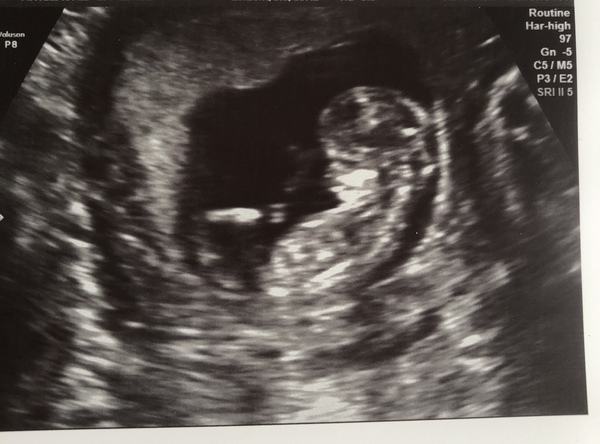

Scan went well this morning, measuring 11+5 so still due 15th Oct, baby was wriggling lots and waving their tiny little fingers. Got my GTT booked for the end of April too. Phew!

Yay!! @imisscoffee amazing. Lovely photo

Awwwwwwwwwwww @imisscoffee lovely!

I'm so glad your scan went well @imisscoffee. What a lovely scan photo - those tiny little fingers are so cute!

Wonderful scan @imisscoffee wonderful to see all ok ❤️